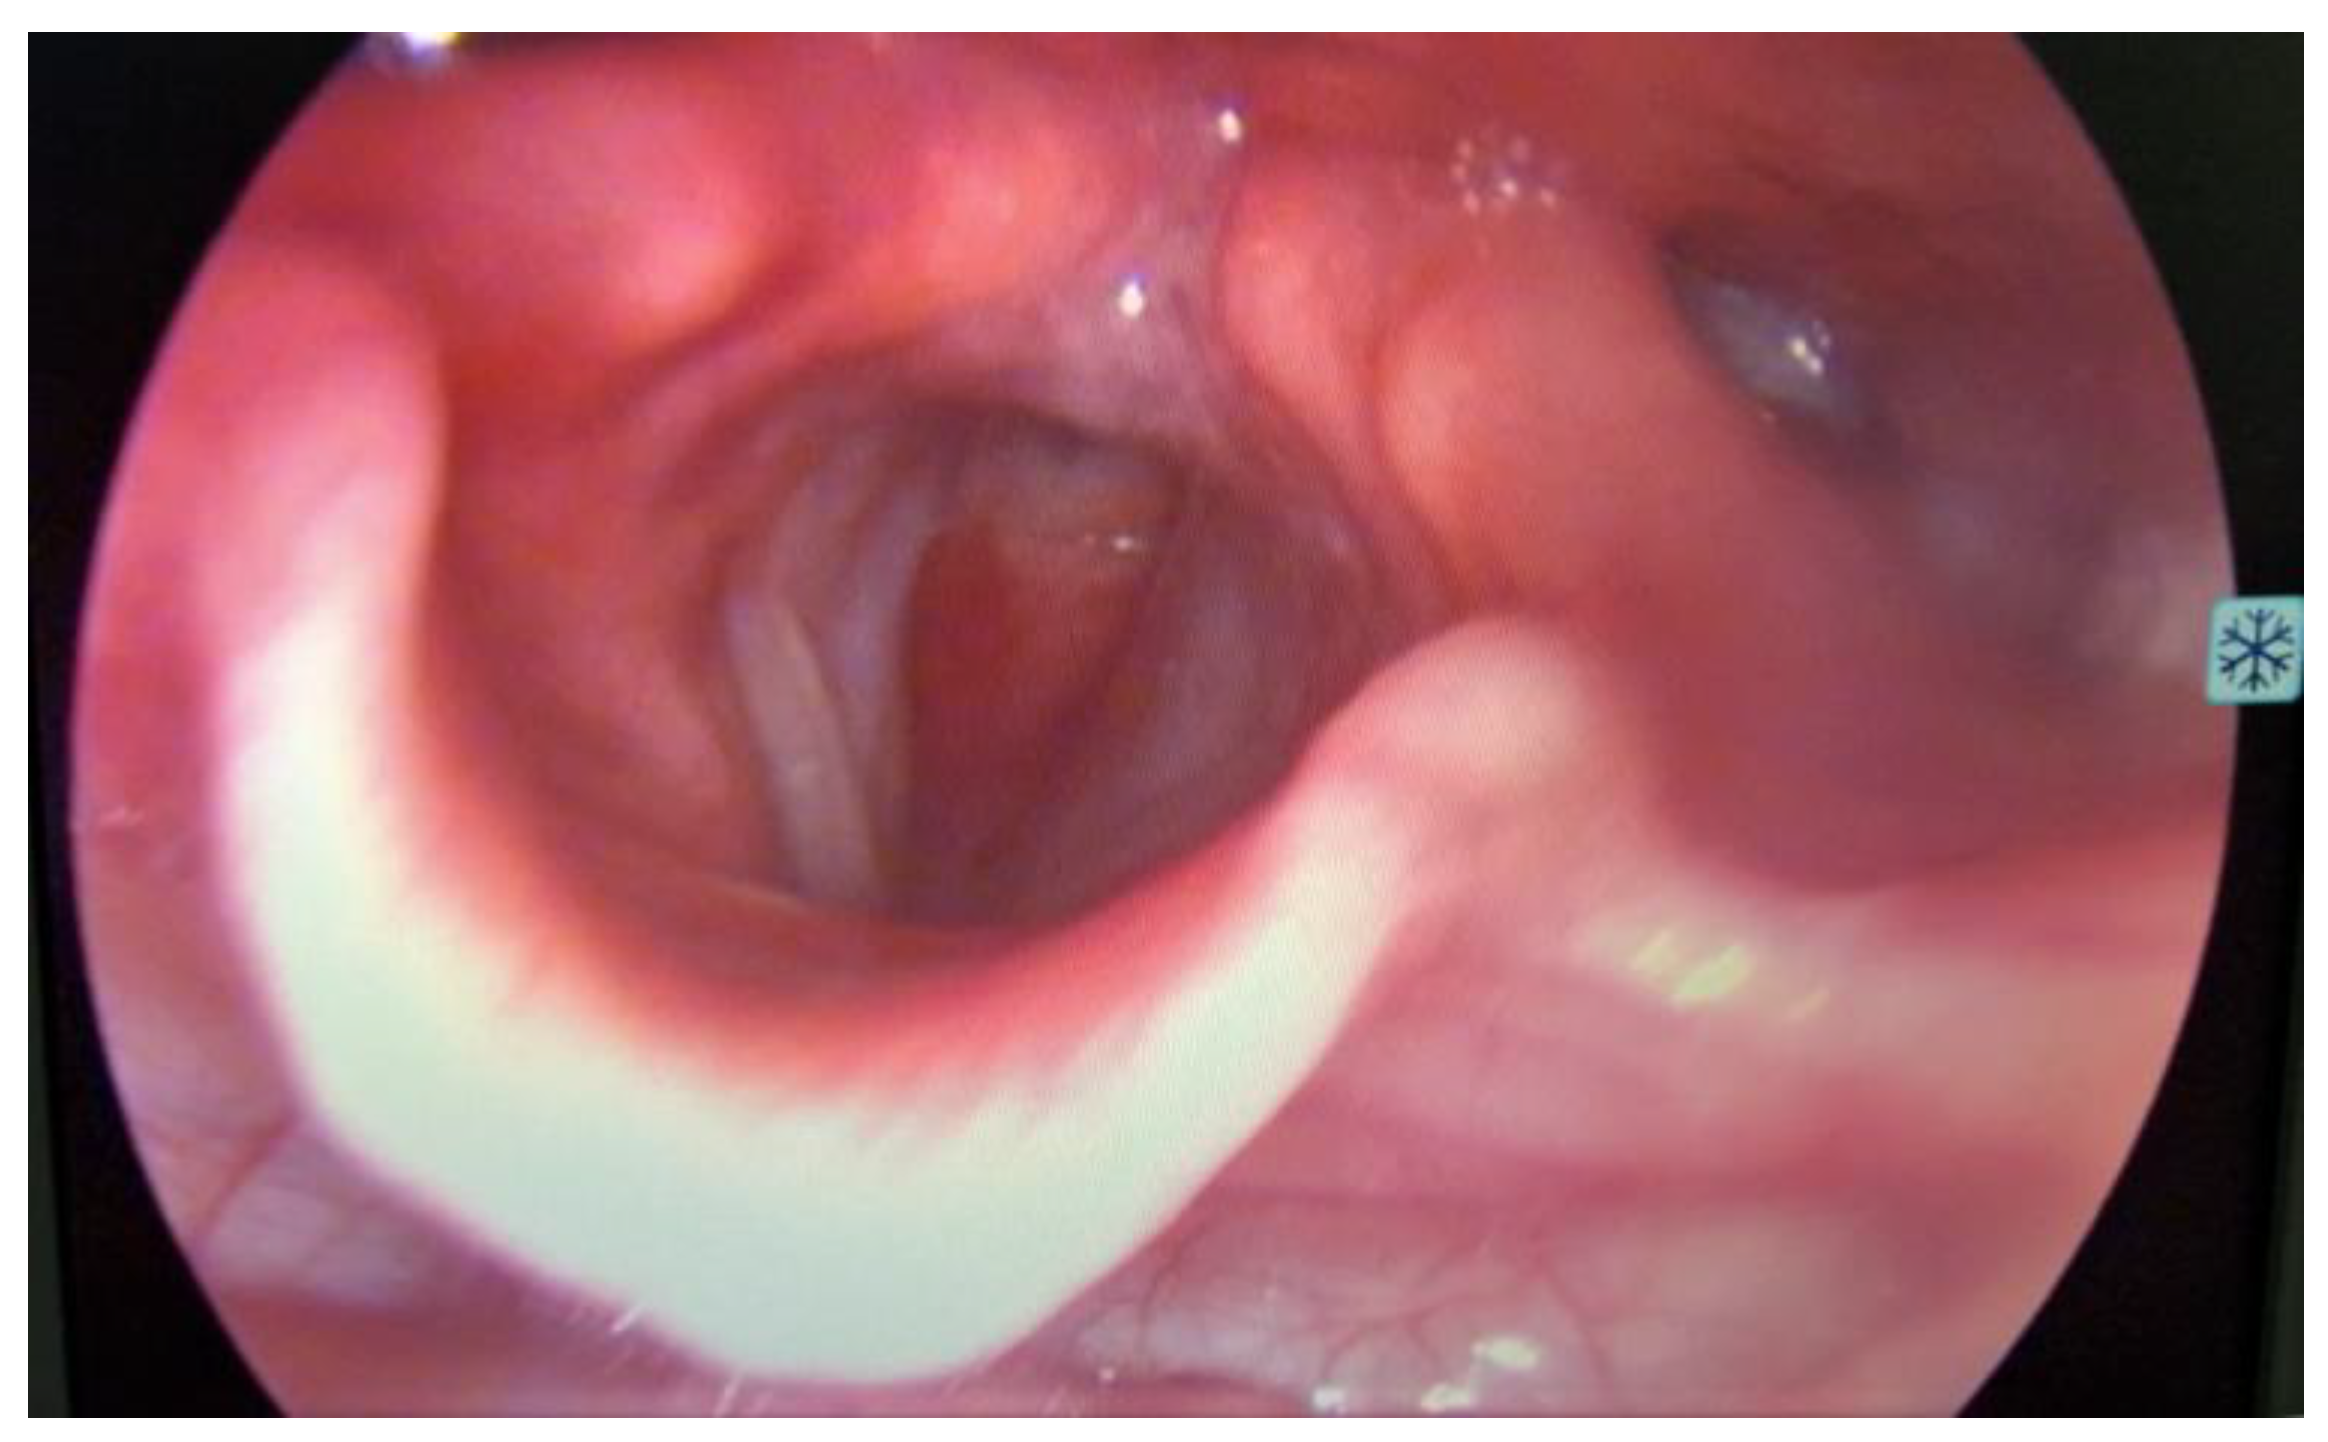

On ORL (Otorhinolaryngology) examination, the patient was in severe respiratory distress, with tachypnea, use of accessory muscles, and showing no lymph nodes or masses at visual inspection and palpation of the neck. At laryngoscopy (Figure 1), supraglottic areas showed a normal appearance, free vocal cords, with preserved mobility, and a subglottic tumor formation located at the level of the first tracheal ring, with marked narrowing of the respiratory space.

Figure 1. Laryngoscopy revealed a bulging subglottic mass, without visualization of the first tracheal ring, with marked narrowing of the respiratory space, normal appearing supraglottic and glottic area.